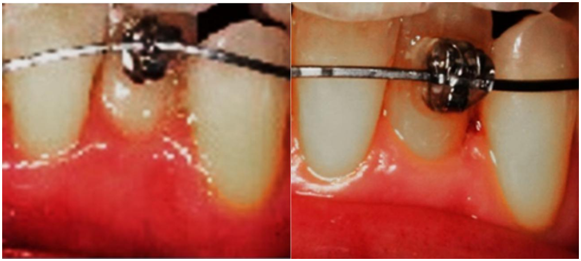

The third case highlights the method and apparatus for the treatment of Orthodontitis ™ and showcases treatment progress of uprighting the mandibular left lateral incisor. Note the straightening of the wire reflects and corroborates the uprighting root movement, the appearance of healthy soft tissue and the elimination of cleft formation previously associated with Orthodontosis™

Figure 8 Treatment progress of uprighting the mandibular left lateral incisor in about 60 days. Note the straightening of the wire reflects and corroborates the uprighting root movement, the elimination of cleft formation previously associated with Orthodontosis™ and the elimination of Orthodontitis™. The teeth may not be completely aligned but gingival inflammation has been eliminated before strict orthodontic and esthetic treatment goals have been fulfilled.